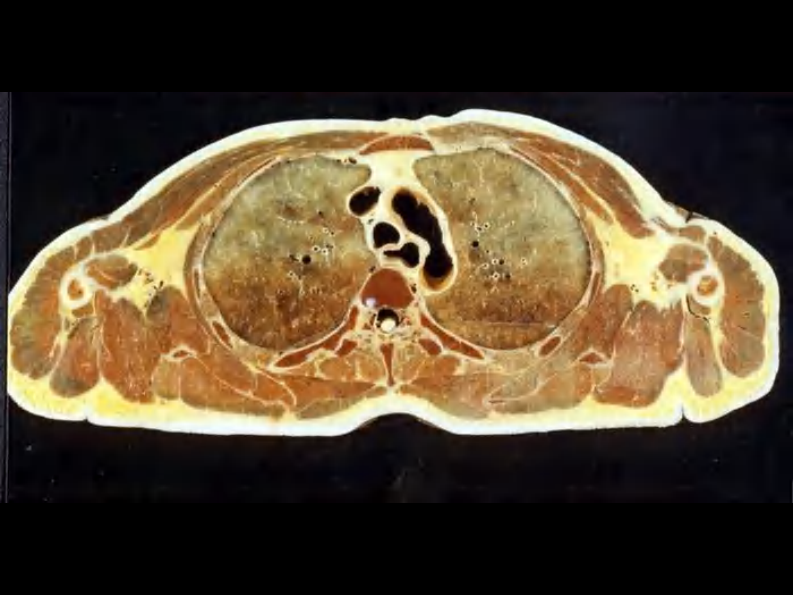

07 纵隔连续横断层解剖及CT.pdf